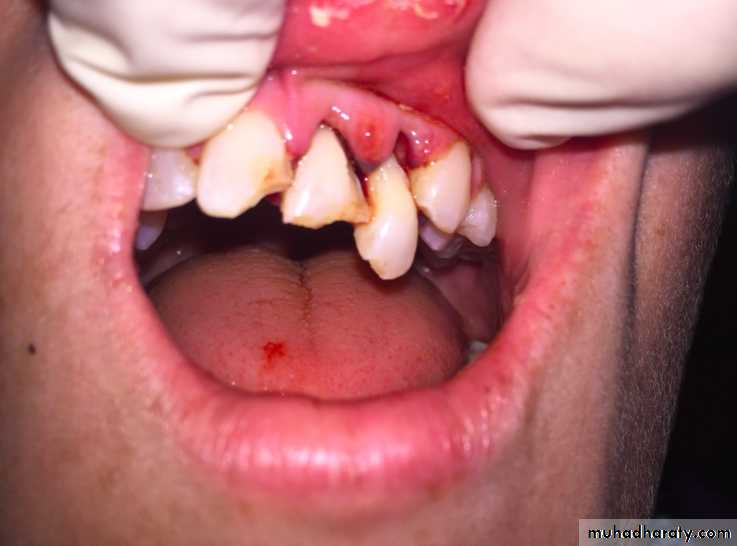

1-Tooth Avulsion

Is a Complete displacement of tooth out of socket, The periodontal ligament is severed and fracture of the alveolus may occur.

Maxillary Central Incisor- Most commonlyavulsed tooth

Mandibular Teeth- Seldom affected

Associated injuries-Fracture of alveolarSocket wall

Associated injuries-Fracture of alveolar socket wall

- Injuries to the lips and gingiva